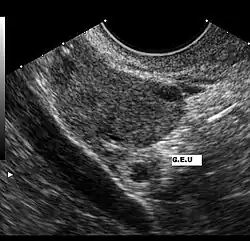

Imagen de un ultrasonido que muestra el saco gestacional de un embarazo extrauterino a la izquierda de las iniciales G.E.U.

El ultrasonido es probablemente la herramienta más importante en el diagnóstico de un embarazo extrauterino, especialmente si se combina con otros métodos. Con mayor frecuencia, se utiliza para confirmar un embarazo intrauterino.[15]​ La visualización de un saco intrauterino, con o sin actividad cardíaca fetal, a menudo es suficiente para excluir un embarazo ectópico.[14]​ La excepción es en el caso de un embarazo heterotópico, la combinación de embarazos intra y extrauterino que, aunque es una situación excepcional, se ven cada vez más frecuentes, entre 1 de 4000 a 1 de cada 30 000 embarazos espontáneos. El estudio de los anexos uterinos por un ultrasonido es obligatorio en pacientes sometidas a estimulación ovárica y la reproducción asistida a pesar de la visualización de un embarazo intrauterino, porque son pacientes que tienen 10 veces mayor riesgo de embarazo heterotópico.

El ultrasonido transvaginal tiene mayor resolución que el abdominal y puede ser usado para visualizar un embarazo intrauterino 24 días después de la ovulación o 38 días después del último período menstrual, que suele ser alrededor de 1 semana antes de los que es posible visualizar un ultrasonido transabdominal. El saco gestacional —un término ecográfico y no anatómico— es la primera estructura que se reconoce en un ultrasonido transvaginal.[14]​ Se ve en el ultrasonido como una zona ecogénica gruesa en torno a un centro hipogénico correspondiente a la reacción decidual trofoblástica que rodea el saco coriónico. Las estructuras que representan a un embrión en desarrollo aún no se pueden reconocer sino hasta una mayor edad gestacional.[16]